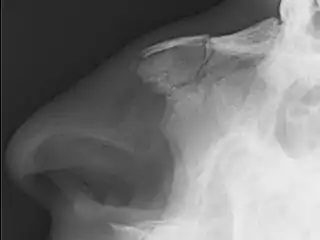

Una fractura nasal,[1] comúnmente conocida como nariz rota, es una fractura de uno de los huesos de la nariz. Los síntomas pueden incluir sangrado, hinchazón, moretones e incapacidad para respirar por la nariz. Pueden complicarse con otras fracturas faciales o un hematoma septal.

Las causas más comunes incluyen asalto, trauma durante deportes, caídas y colisiones de vehículos motorizados. El diagnóstico generalmente se basa en los signos y síntomas y, en ocasiones, puede confirmarse mediante una radiografía simple.